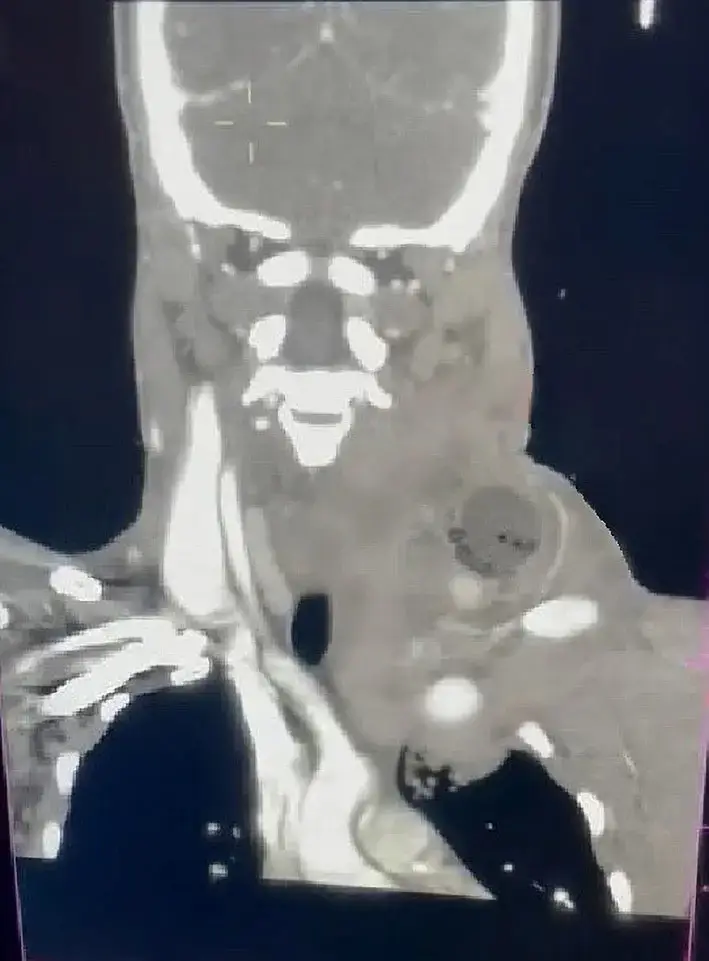

Although utilized by trauma services throughout the world, most published medical literature on the technique involves specifically penetrating neck wounds with ongoing bleeding. This technique has been extensively utilized and studied in South Africa, which is responsible for most of the published medical literature. There, in bleeding neck wounds (139 patients) the most common mechanism of injury was stabbings at 91%, and gunshot wounds made up the remainder. 2

Placement of an 18 to 20 French urinary catheter into a bleeding neck wound to the point of bleeding, then inflating with sterile water/saline until the bleeding stops or resistance to additional inflation is felt, is 92% effective in controlling bleeding across multiple studies. 2, 3, 4, 5, 6

Many of the South African trauma service protocols leave the catheter, inflated, and in place for 24 hours2 or 48 hours.9 At that time they deflate it and if there is no ongoing bleeding it is removed and the patient never formally undergoes surgery, even with some minor arterial injuries identified on CT angiogram of the neck.2 From the standpoint of prolonger casualty / field care, this could be very beneficial.